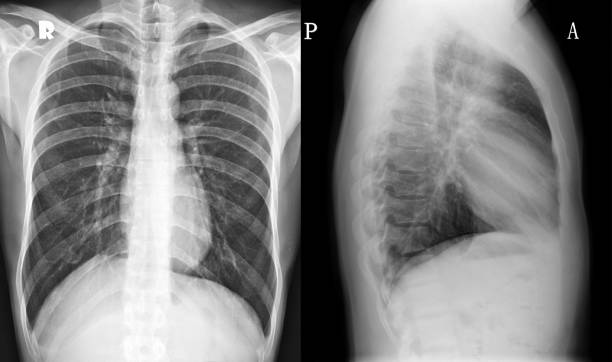

Images And Video Resources

Haematuria Clinic: Initial Consultation and Investigations